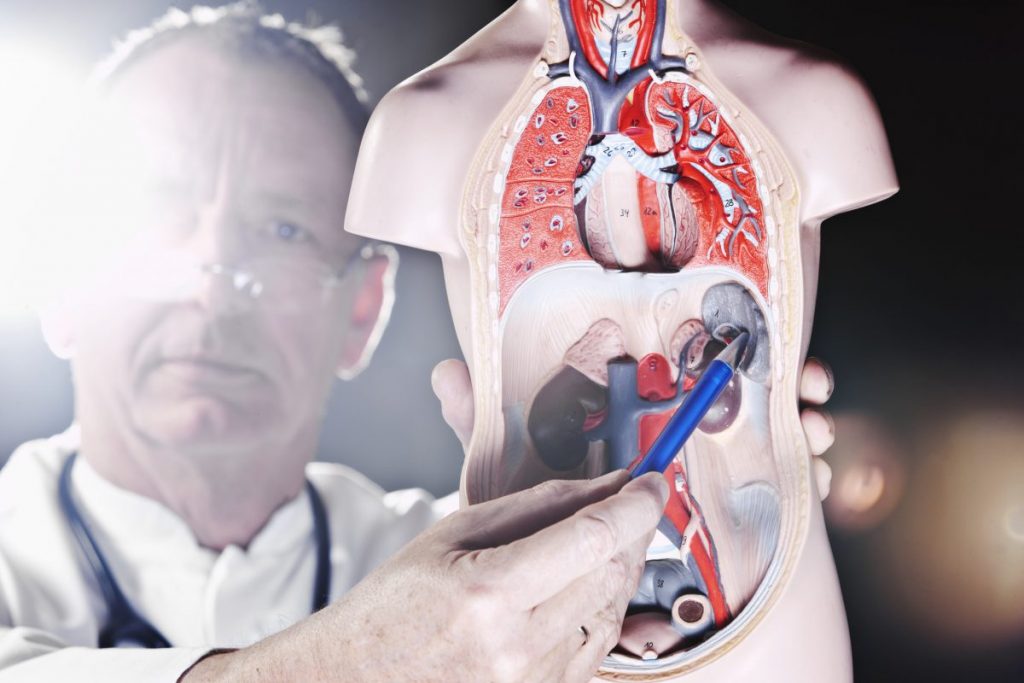

قیمت: 45٬000 تومان - دسته بندی فایل: پاورپوینتپاورپوینت سندرم بود کیاری چیست

خرید پاورپوینت حرفه ای با موضوع سندرم بود کیاری چیست از لوکس فایل